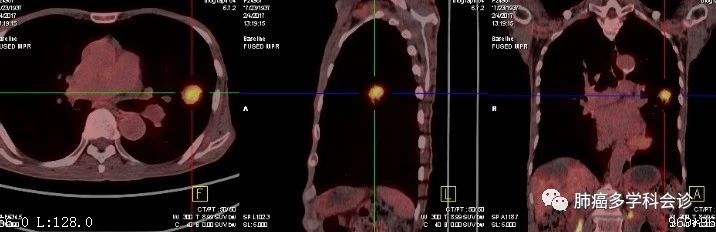

PET-CT:右肺上叶软组织代谢活跃,符合肺癌。其它处未见转移征象

肺部肿块接受 SBRT 放疗后逐渐消退。

2018年6月出现头晕头痛,MRI:脑双侧额叶囊实性转移灶。